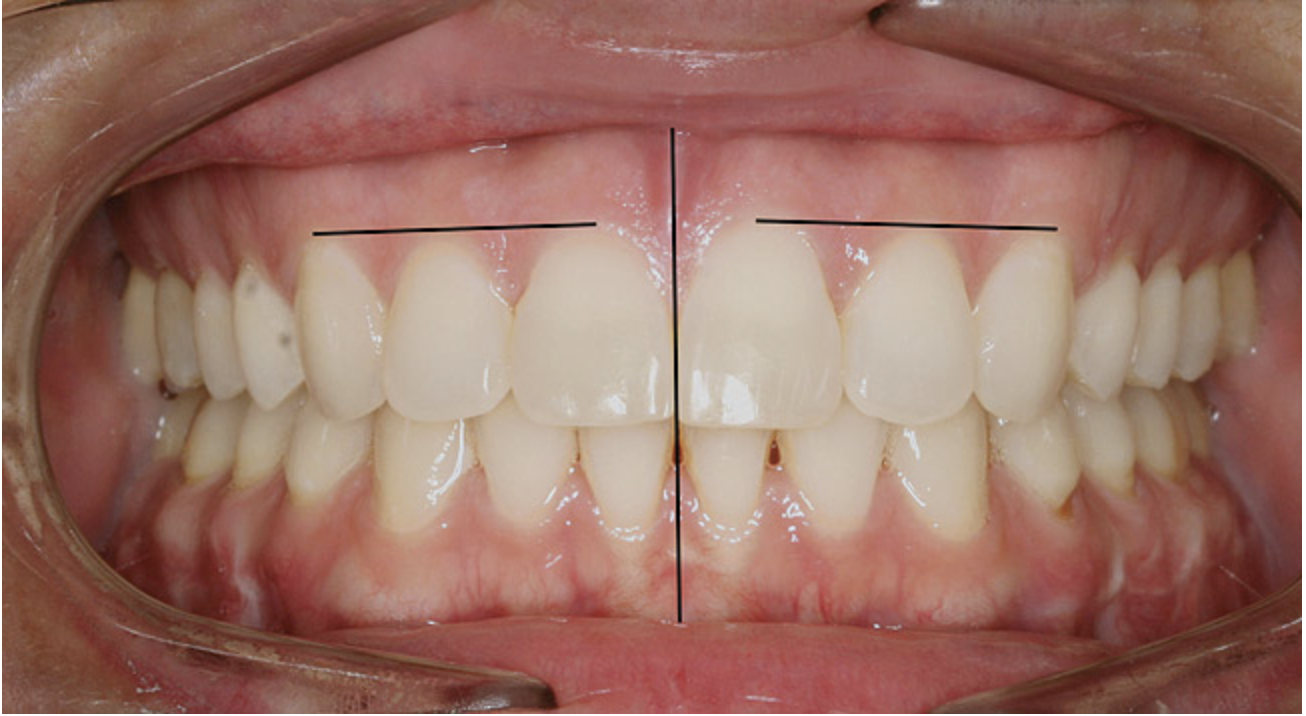

The dental midline can be improved within limits by restorative procedures. However, if orthodontic alignment is to be performed, the orthodontist plans treatment to ensure the position and vertical axis of the midline is harmonious with the facial esthetics (Figure 1).

Figure 1  Dental midlines should be as close to coincident as possible. Gingival height of maxillary lateral incisors should be even with a line between the gingival height of the central incisor and canine to 1.5 mm below that line.

Figure 1